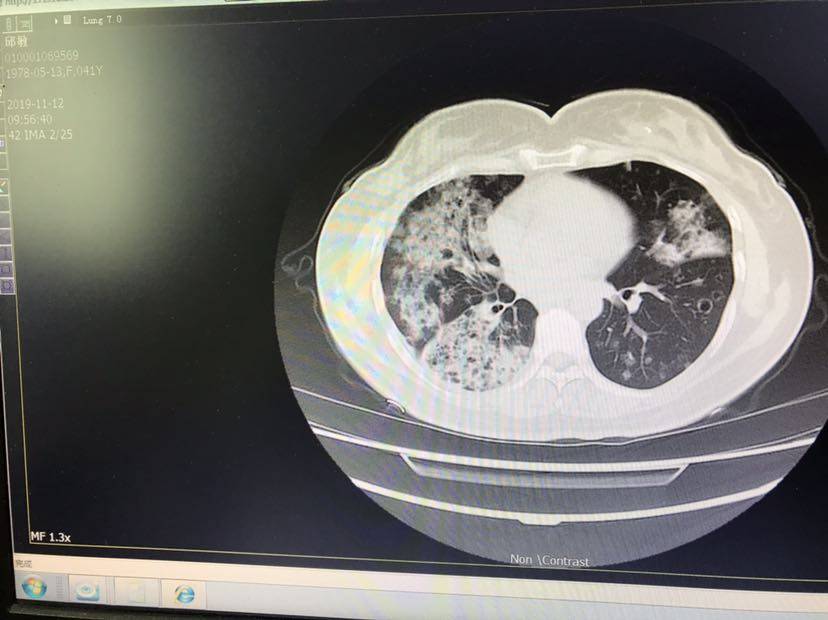

白天做了第24次化疗的我整夜忽冷忽热,想吐吐不出来,喝了n多杯水,果汁,水果,依然难受的半夜这个时间还没办法睡,自从我知道自己不仅有kras突变还有stk11后,绝望了一阵子,从9月后,我一度空窗,期间只吃了中药,体感倒是很好,上周还去了三亚,满心以为自己也许收益于中药了,现实却给我狠狠一巴掌,我在三亚时突然咳嗽超级厉害,咳到自己呕吐甚至小便失禁,心觉不好赶紧回家,果然,又弥漫的更多了……我的肺呀~太让我伤心了,我努力好好吃并调整我的心态,为什么癌细胞依然这么嚣张,它们难道不知道搞垮了我它们也会一起陪葬的吗?

这次回头用培美加卡铂,还加了安罗,单培美八九月试过,是不行的,没控制住,我也佩服自己的心大,居然停了这么久只依靠中药的勇气